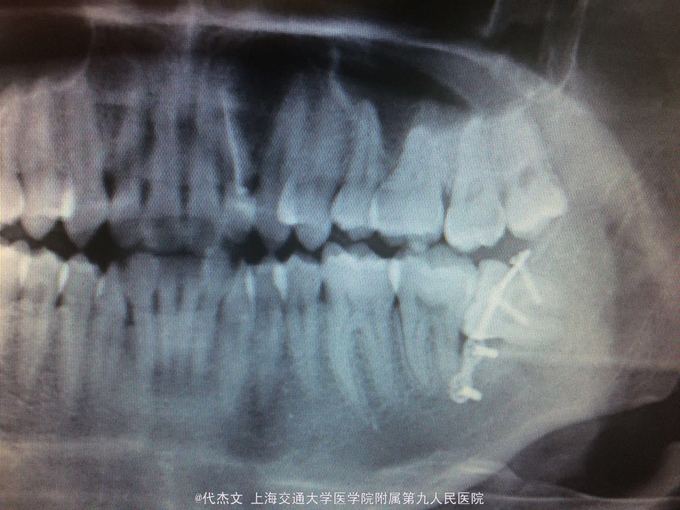

38阻生,牙龈无红肿。颊测黏膜下可触及钛板。X线片示38近倾阻生。固位钛板钛钉在位。

诊断:左下颌骨折术后钛板留置。38阻生;处罝:全麻下38拔除后拆除钛板。术中见一个钛钉松动。